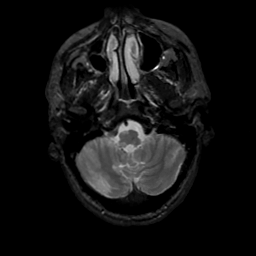

MR Study #13, May 19, 1991 -- Slice #8

[Home][Help][Clinical][Tour 1][Tour 2] Slice 8